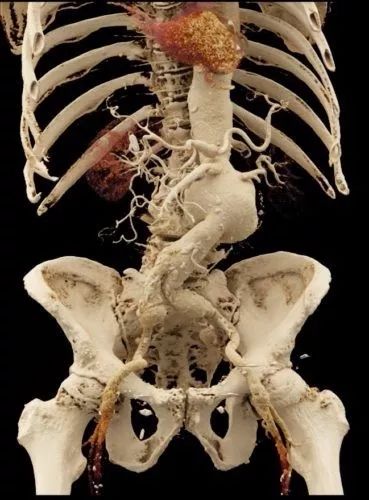

使用电影渲染实现解剖结构可视化

在约翰·霍普金斯大学,Elliot Fishman博士和Siemens的研究人员开发了一种名为“电影渲染”的新方法,使用基于物理性质的光扩散模拟,以生成逼真的人体图像。电影渲染受到了电脑动画电影中使用的计算机绘图和GPU技术的启发,使用全局照明,通过数千条直接和间接光线制作出一张逼真的图像。

电影渲染可以生成逼真的图像,这些图像有可能更准确地描绘解剖细节和复杂的解剖结构。“电影渲染:原理、应用和在 CT 中的观察结果”,Elliot K.Fishman,RSNA 2017 科学展。

通过这些令人惊艳的图像,放射科医生可以识别出细微的纹理变化和周围解剖结构的空间关系。另外,Fishman博士和霍普金斯的团队正在研究深度学习算法是否可以从电影渲染的图像保真度中获得启发。